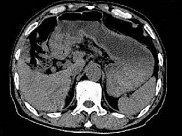

- 单项选择题根据所提供的图像,最可能的诊断是 ( )

A、胃淋巴瘤

B、胃平滑肌瘤

C、胃窦癌

D、胃窦炎

E、以上都不是